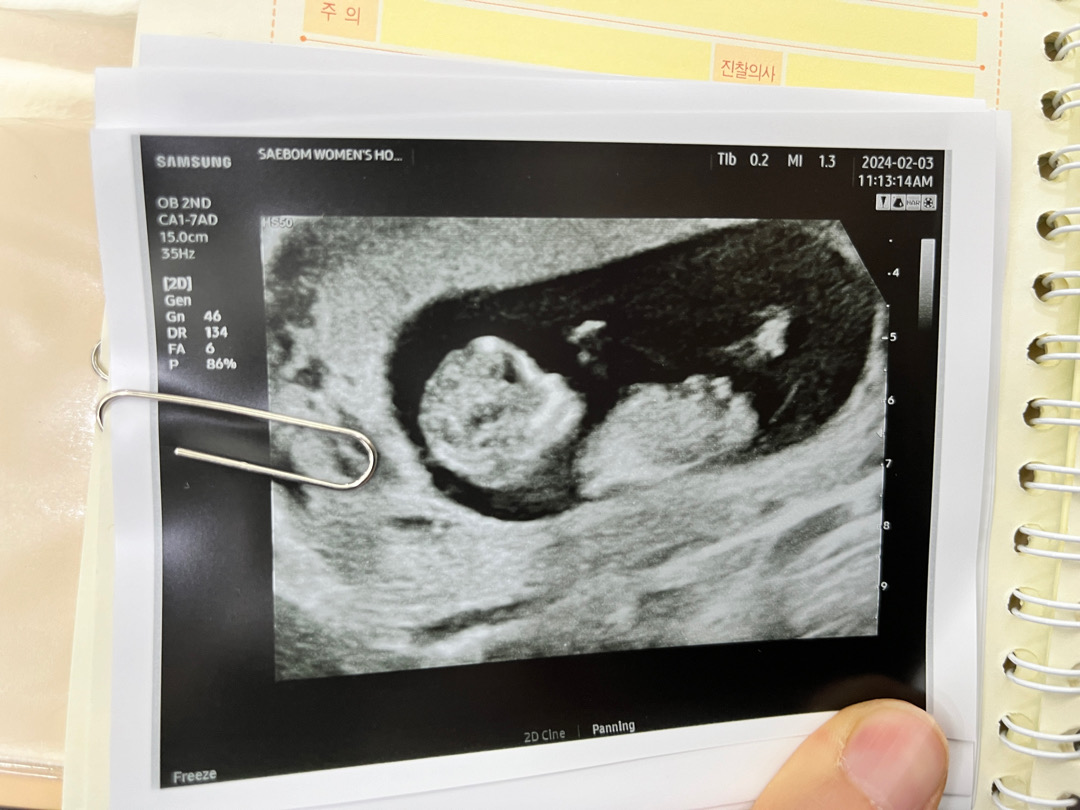

각도법 고수님들ㅎㅎㅎ성별확인 부탁드려요

성별 알 수 있을까요?